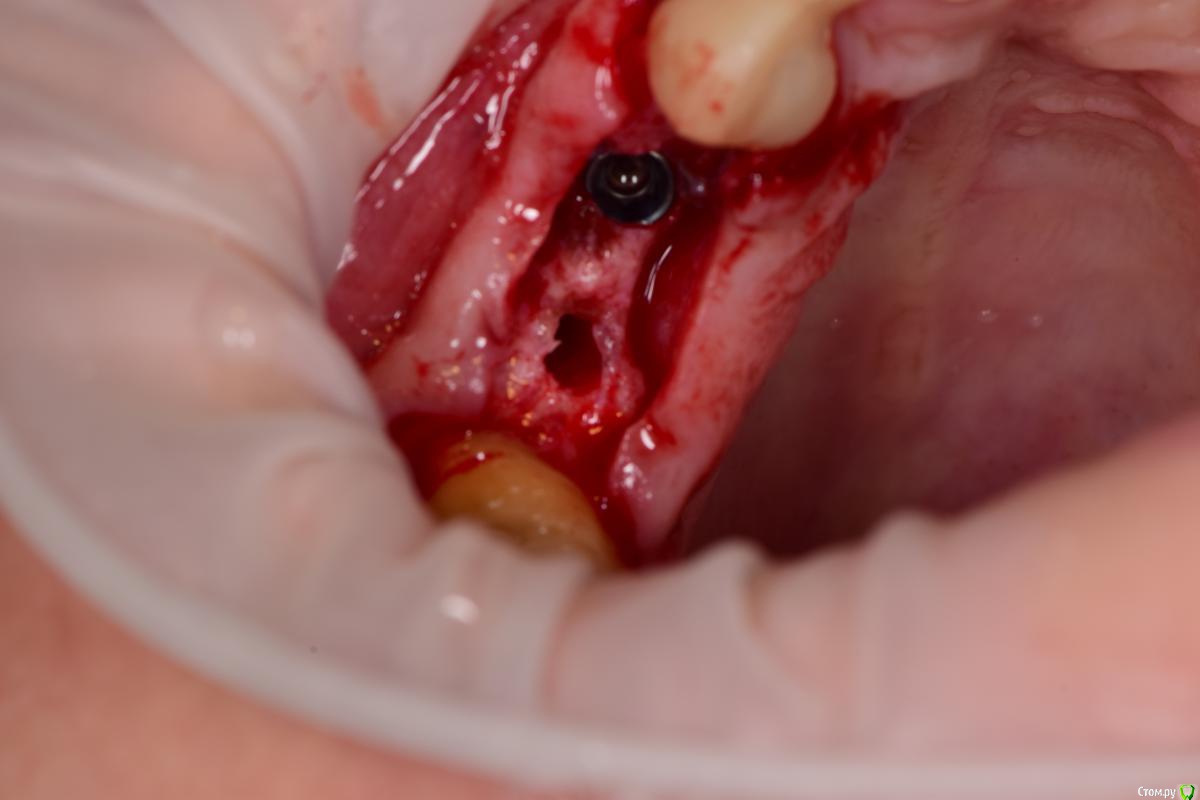

Петр Бриньковский Опубликовано 20 мая, 2017 Поделиться Опубликовано 20 мая, 2017 Южнокорейские импланты с использованием спейсеров и прикручиваемых титановых сеток при НКРзалесных ренген.bmp 4 Ссылка на комментарий

Петр Бриньковский Опубликовано 21 мая, 2017 Автор Поделиться Опубликовано 21 мая, 2017 (изменено) Чем сетки покрывали? Почему выбрали этот метод?PRF мембраны, метод работает достаточно неплохо , в последнее время очень часто так делаю после того как в Корею осенью к доктору Паку на конференцию съездил. Сетки разных форм и ширины и с помощью спейсеров можно увеличиваться немного по высоте(1-3 мм). Каркас достаточно надежный и впоследствии достаточно легко удаляются без сильного отслоения, а на сами спейсеры прикручивается дополнительно формик(можно одномоментно). Изменено 21 мая, 2017 пользователем Петр Бриньковский Ссылка на комментарий

Петр Бриньковский Опубликовано 21 мая, 2017 Автор Поделиться Опубликовано 21 мая, 2017 а что под сетки?и где забор?(если только ауто)Под сетки "Mega-Oss" и поверх мембраны PRF Ссылка на комментарий

Петр Бриньковский Опубликовано 22 мая, 2017 Автор Поделиться Опубликовано 22 мая, 2017 Синий имплантат похож на учебный осстем. Что за фирма?Это синее покрытие имплантов Mega Gen, в данном случае Ayn One Ссылка на комментарий